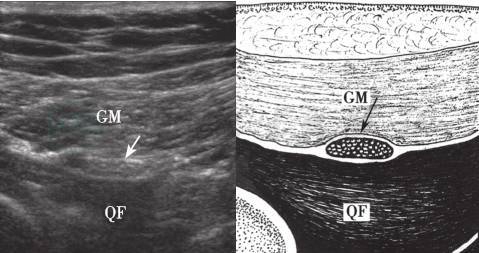

2.大腿后部

大腿后部的坐骨神经位于股二头肌与大收肌之间(图10-30,图10-31),此处的坐骨神经病变的定位,也可自臀部或腘窝处做连续的横断面扫查移行至此处。

图10-30 大腿后部坐骨神经短轴声像图

BF:股二头肌;AM:大收肌;箭:坐骨神经

图10-31 大腿后部坐骨神经长轴声像图